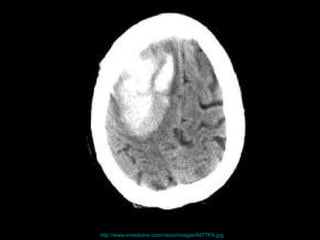

致命的運動傷害 , 包括 猝死 嚴重脫水 熱衰竭 外傷性腦傷

http://www.revilocartoons.com/sketchbook%20/Concussion%20time.jpg

http://www.emedicine.com/neuro/images/687TPA.jpg